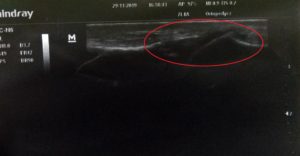

Chẩn đoán siêu âm - bong gân khớp cổ chân trái đầu tiên. Trong hình có dịch xuất tiết, tổn thương bao khớp và dây chằng chéo trước.